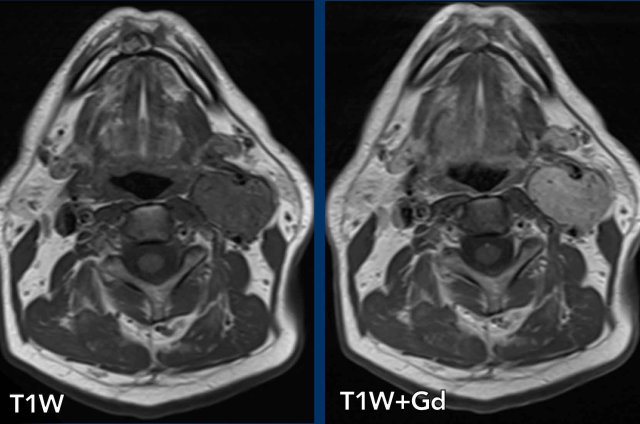

Imaging protocol

CT and MRI can be complementary, but CT is preferred in the acute setting and for evealuation of vascular and osseous injury and pulmonary mass

MRI is preferred for imaging of the brain and spinal cord.